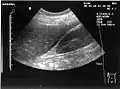

A normal ultrasonographic view of Morison's pouch. The bright line is the capsule of the kidney; there is no fluid present and hence no visible space. -